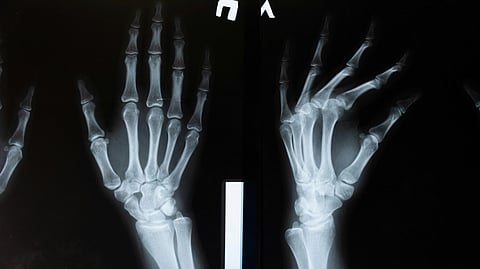

X-ray image of two hands, showing bones in detail.

Some lovers try positions that they can’t handle – I’m referring to the bones of the wrist, of course. The phrase is a classic mnemonic used to remember the eight carpal (wrist) bones – scaphoid, lunate, triquetrum, pisiform, trapezium, trapezoid, capitate and hamate – whose initials form the memorable sentence.